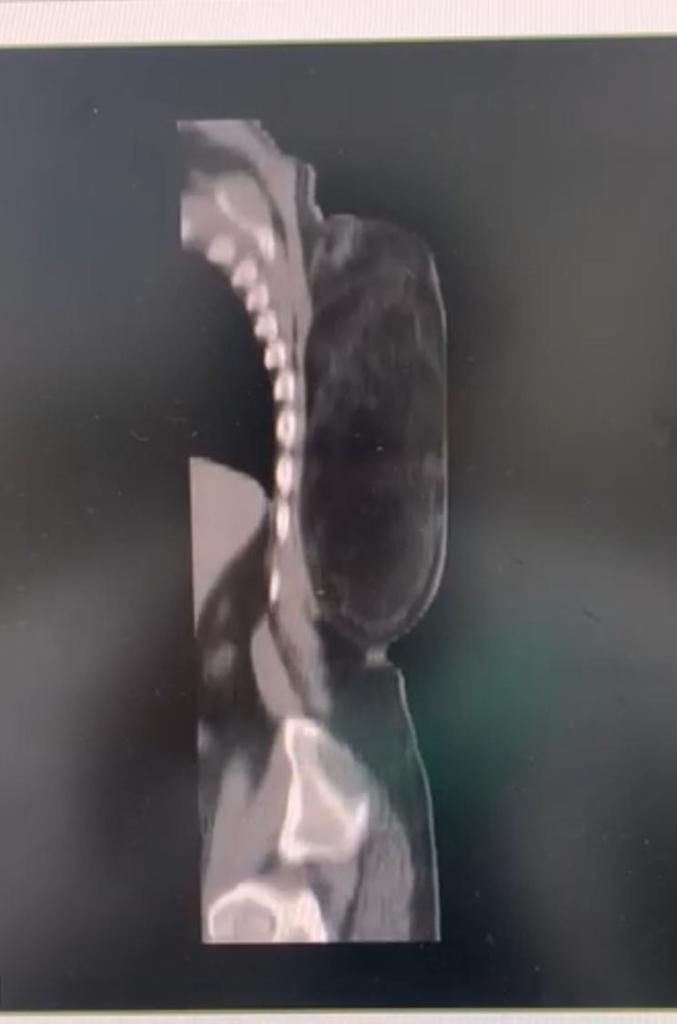

تمكن فريق طبي جراحي في مستشفى الملك فهد بجدة في إنقاذ حياة مريض في العقد السادس من العمر، وذلك بعد تمكنهم من إجراء عملية جراحية لإزالة واستئصال ورم مرتجع كبير الحجم في ظهره وممتد إلى جوار عضلات العمود الفقري.

وأوضح الفريق الطبي الجراحي  بالمستشفى أن حجم  الورم يبلغ ٤٠ سم في ٣٠ سم حيث يقارب وزنه ثلاثة كيلو، وأشاروا أيضاً أن المريض كان يعاني من هذا التورم الضخم من فترة طويلة و لا يستطيع ممارسة  نشاطه اليومي و النوم على ظهره لمدة ثلاث سنوات، مبينين أن المريض الآن وبعد إجراء العملية الجراحية له و إزالة الورم بدأ يتماثل للشفاء وبصحة جيدة، وسوف يحتاج المريض لإستكمال باقي العلاجات الطبية المقررة له بعد العملية للإستشفاء